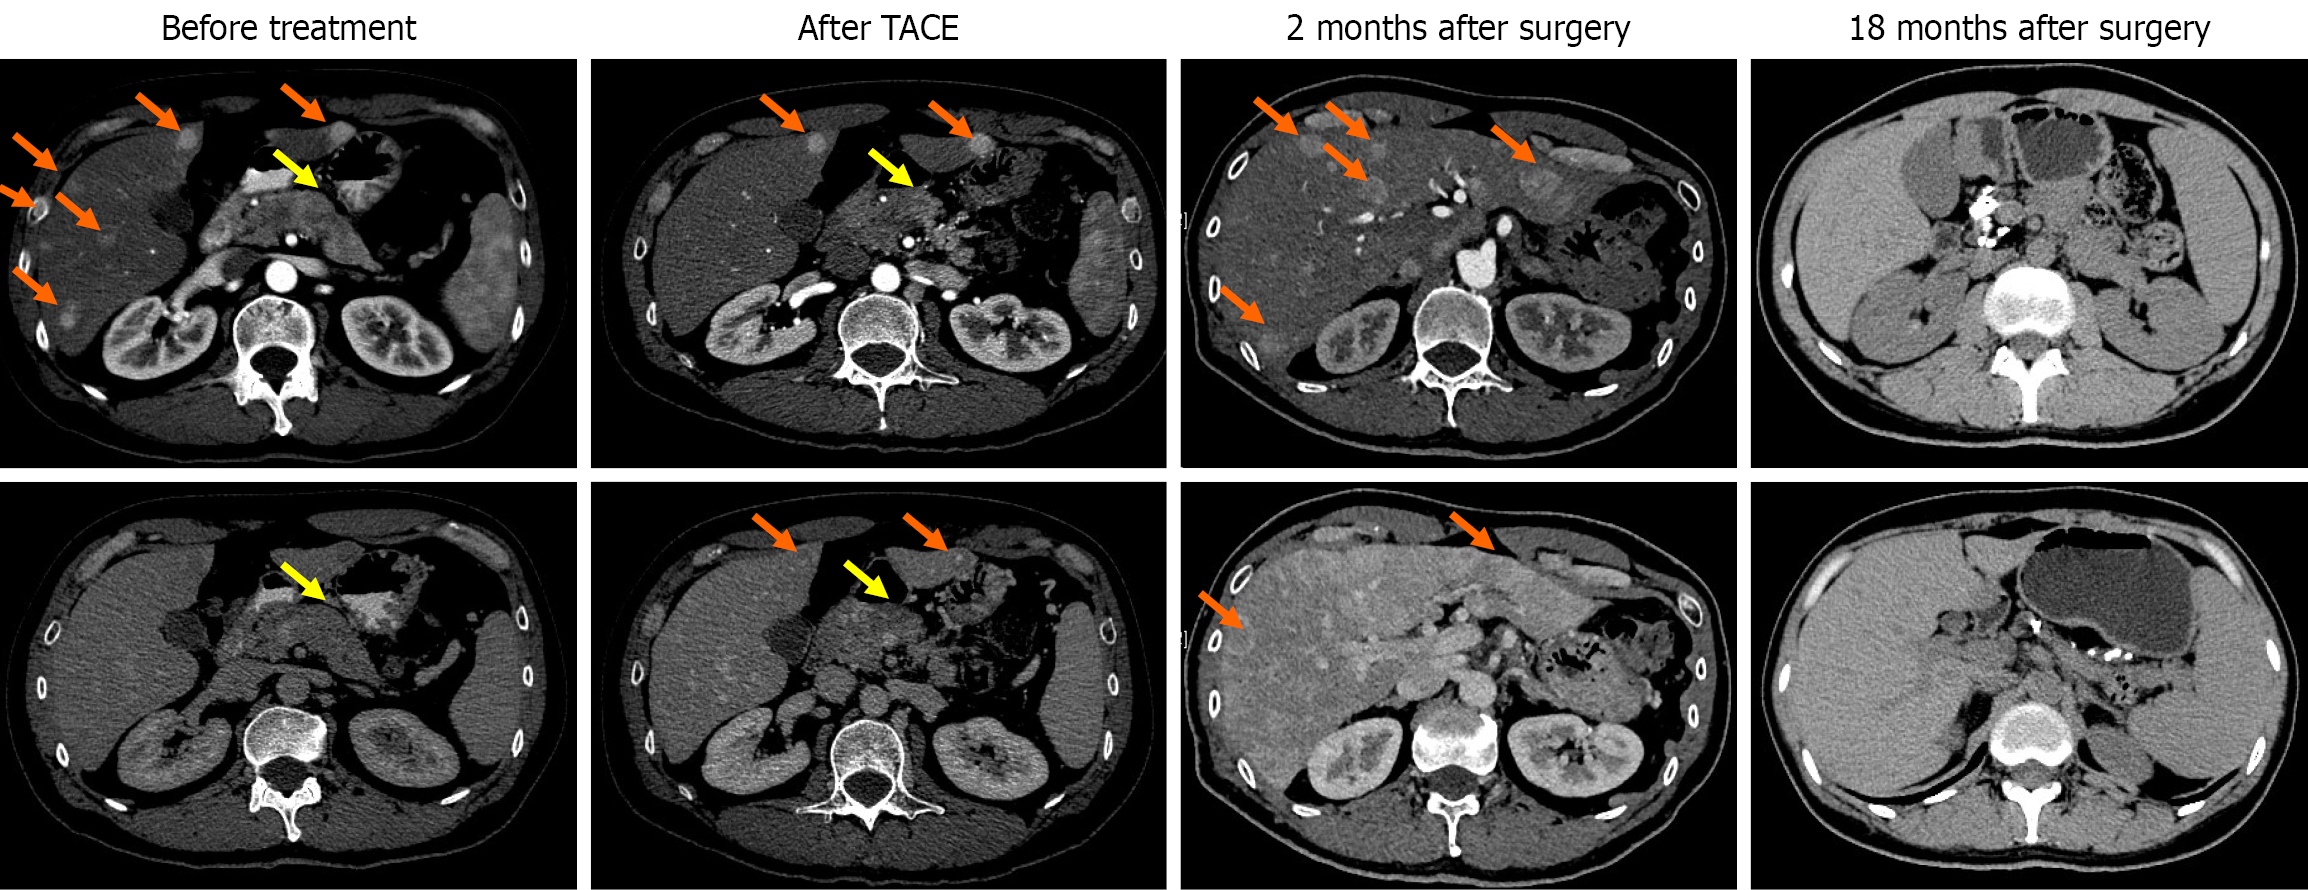

Figure 1 Computed tomography images of the patient before treatment, after transarterial chemoembolization, 2 months and 18 months after surgery.

The orange arrows point to the liver lesions, and the yellow arrows point to the pancreatic lesions. TACE: Transarterial chemoembolization.